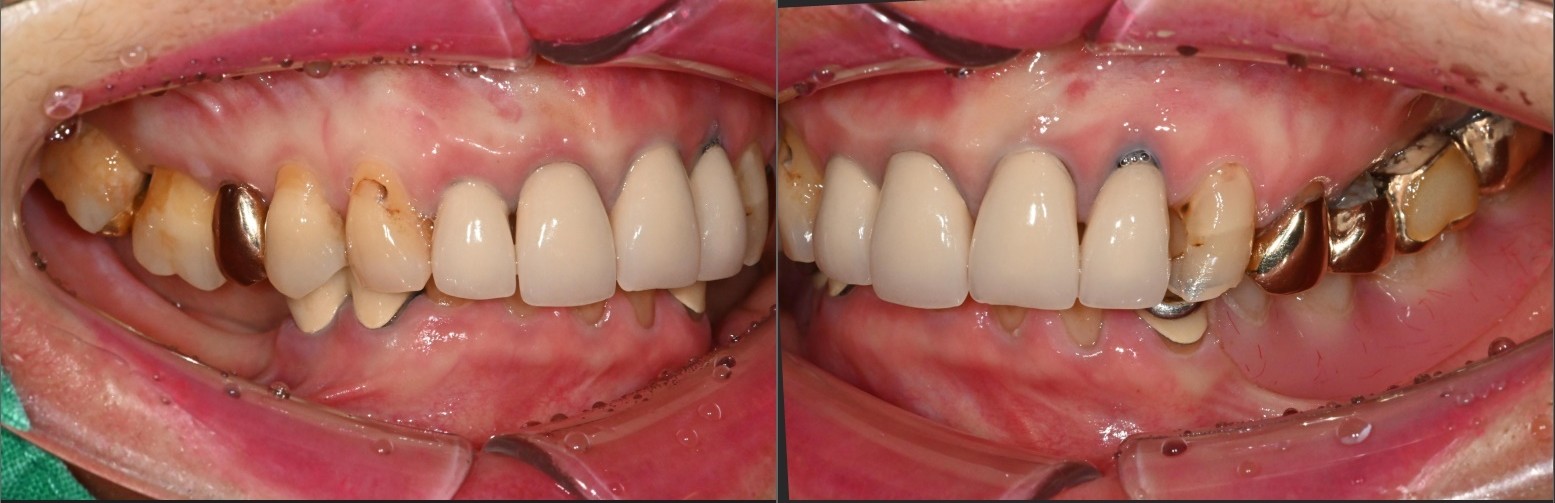

겉으로 보기에도

잇몸이 많이 부어 있었지만,

엑스레이 사진상에서도

치조골이 상당 부분 소실된 것

확인되었습니다.